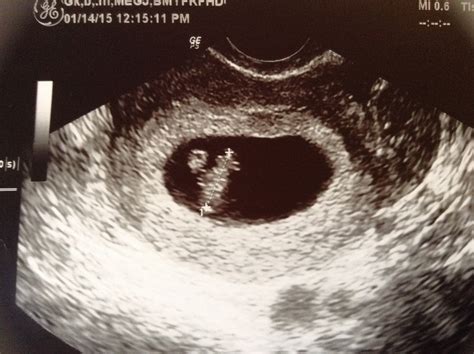

An 8 week sonogram is an ultrasound examination performed around the eighth week of pregnancy. This non-invasive procedure uses high-frequency sound waves to create images of the fetus and the uterus. The primary goal of an 8 week sonogram is to confirm the pregnancy, determine the gestational age, and assess the fetus’s development.

• Determining Gestational Age: Measuring the crown-rump length (CRL) of the fetus helps determine the exact gestational age, which is essential for monitoring the pregnancy’s progress.

The results of an 8 week sonogram are interpreted by a trained ultrasound technician and reviewed by an obstetrician. Key findings include:

• Gestational Age: The CRL measurement helps determine the exact gestational age, which is crucial for monitoring the pregnancy’s progress.

• Fetal Heartbeat: The presence of a heartbeat is a positive sign of a viable pregnancy.